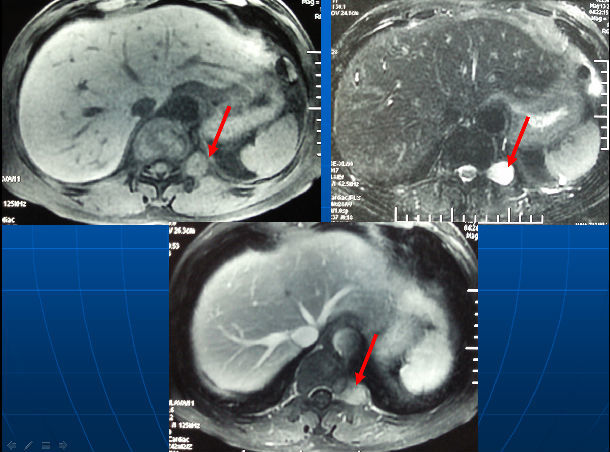

左侧腹膜后神经鞘瘤